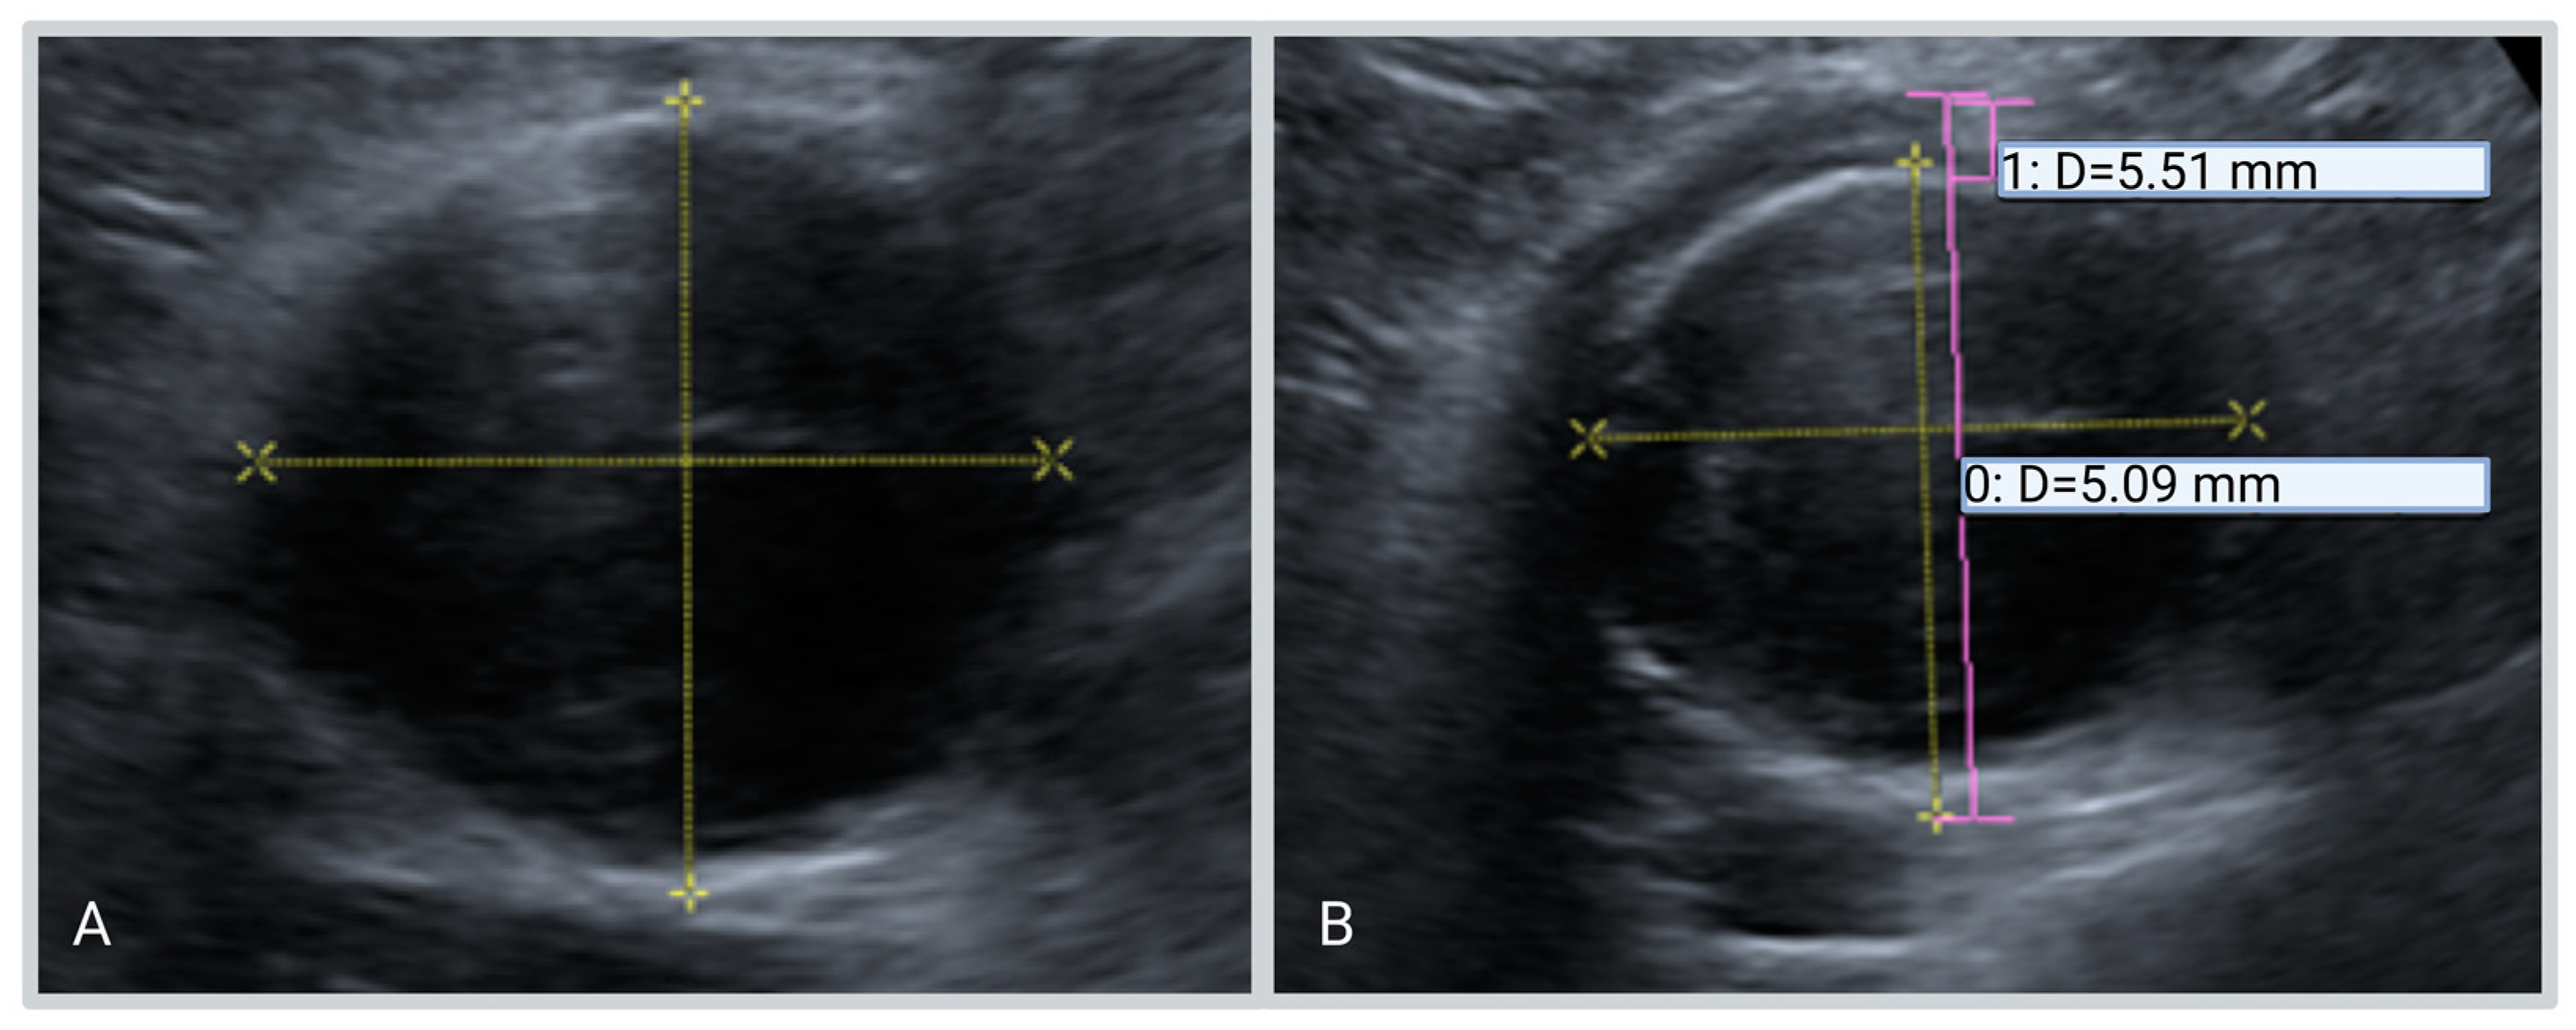

- The maximum anteroposterior diameter of the aorta including the hypo-echogenic layer outside the calcified layer.

- The anteroposterior diameter of the aorta excluding the hypo-echogenic layer (up to the calcified layer)

- The thickness of the hypo-echogenic layer at the anterior site of the aneurysm.